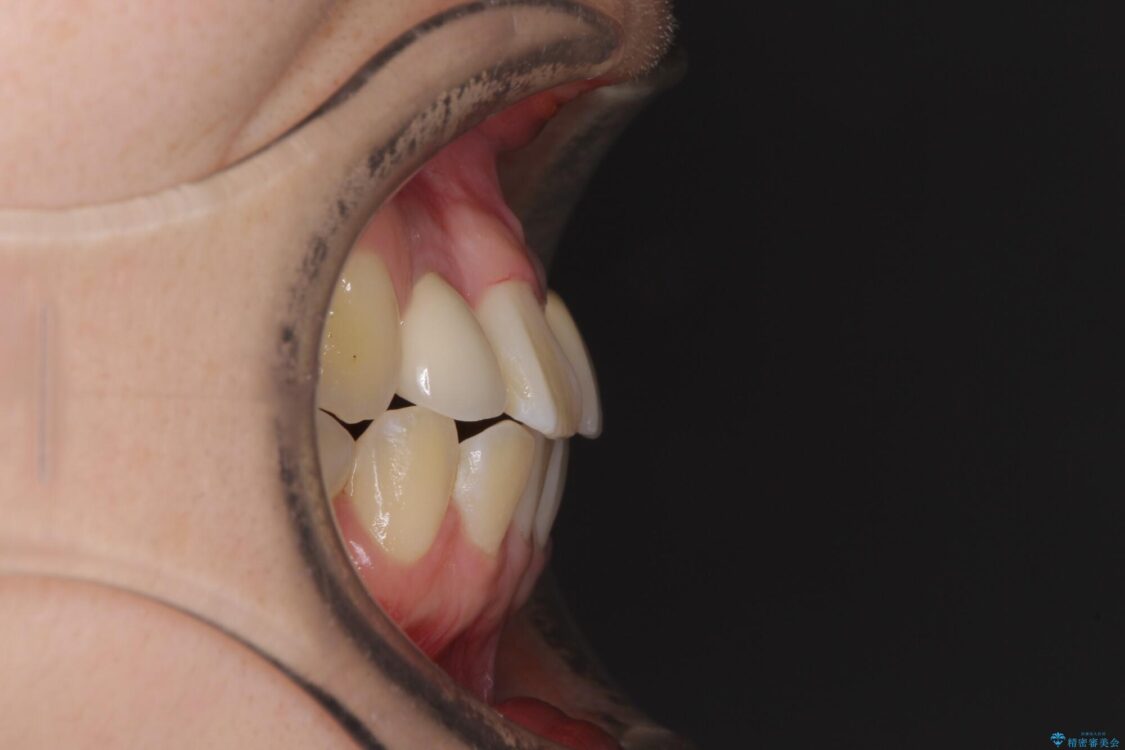

治療前

• 虫歯治療ついでに歯並びの後戻りを改善 インビザラインによる矯正治療 治療前画像

奥歯が痛いとのことで来院された患者様です。

治療計画

上顎親知らず周辺の炎症と、神経組織の失活した歯の炎症による痛みが認められたため、親知らずの抜歯と根管治療を行いました。

根管治療を行った歯はクラウンによる補綴治療が必要となりますが、高校生の頃に行った矯正治療の後戻りも気になるとのことで、補綴治療を行う前に矯正治療を行うこととしました。

後戻りは軽度であり、インビザラインにて歯列を整え、その後にオールセラミッククラウンにて補綴治療を行うこととしました。